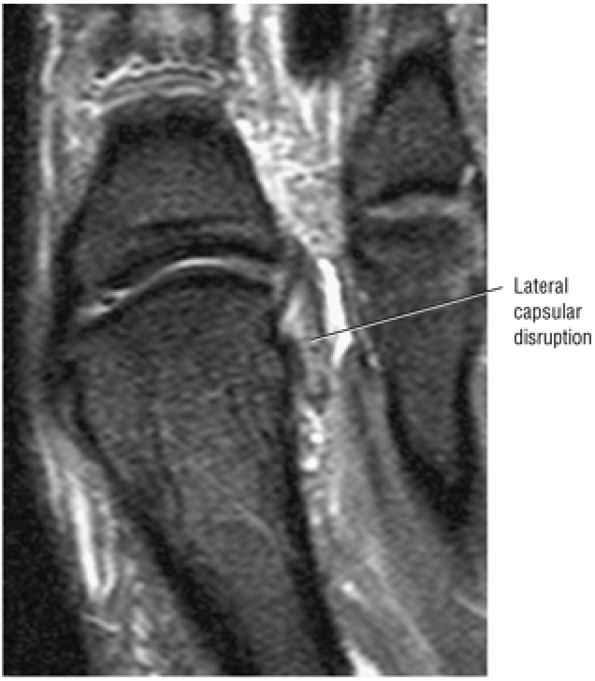

![]() |